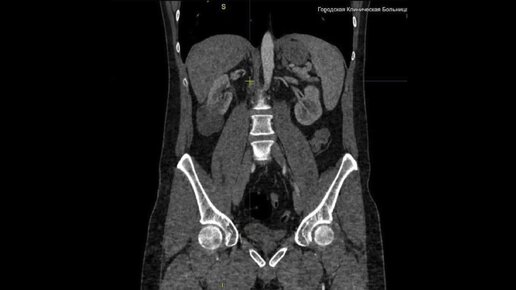

О пользе УЗИ в дифференциальной диагностике кист почек.